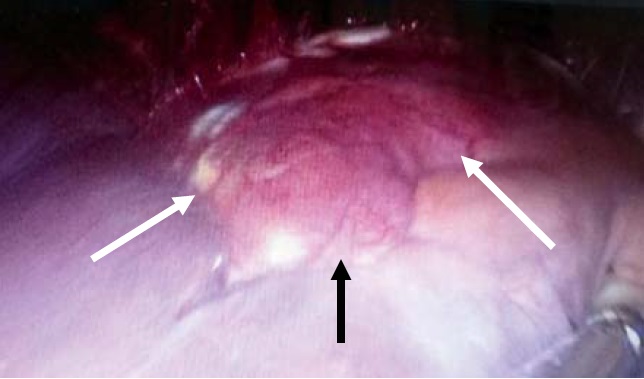

Результаты и их обсуждение. Военнослужащий срочной службы Т., 1989 г.р., в Вооруженных силах РФ с 20 апреля 2015 г., проходил службу в качестве повара воинской части. На фоне полного благополучия в январе 2016 г. проходил медицинское освидетельствование для поступления на военную службу по контракту. При ультразвуковом исследовании (УЗИ) выявлена киста печени диаметром около 10 см. С целью дополнительного обследования был направлен в военный госпиталь по месту службы. При обследовании в анализах крови патологии не выявлено. Вирусные гепатиты В и С не выявлены, антитела к вирусу иммунодефицита человека отрицательные. Выполнен иммуноферментный анализ на эхинококк, который был положительным. При контрольном УЗИ определялась многокамерная киста правой доли печени диаметром около 10 см (рис. 1).

Рис. 1. УЗ-картина многокамерной эхинококковой кисты (диаметр 10 см)